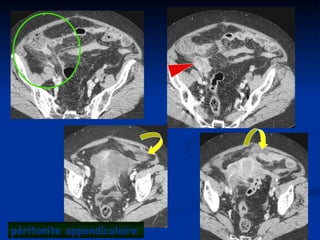

péritonite appendiculaire

péritonite sur appendicite pelvienne

Les formes évolutives(2) Les formes évolutives (2)  Les péritonites Les péritonites  En 1 temps : tableau d’app typique puis aggravation En 1 temps : tableau d’app typique puis aggravation  En 2 temps : tableau d’app typique, accalmie, puis aggravation En 2 temps : tableau d’app typique, accalmie, puis aggravation  En 3 temps : app, plastron, abcès,péritonite En 3 temps : app, plastron, abcès,péritonite  Clinique Clinique  Douleurs diffuses Douleurs diffuses  Température à 40° Température à 40°  Contracture Contracture  TR,TV TR,TV  Etat de choc?? Etat de choc??